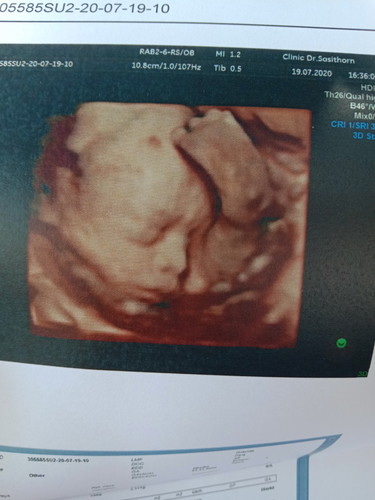

6เดือนแล้วนะ พึ่งรุ้เพศ เครียดอะไรคะ อดขำไม่ได้ คุณหมอบอกกะจู๋ ชัดมากเลยคะแม่ 24W

พอคุณหมอซาว คุณหมอบอกว่าน้องเอาขาก่ายหน้าเลย แม่นี่ขำเลยคะ555

ขาก่ายหน้าผากเลย คิดอะไรอยู่นะ

ท่าแรกที่เจอ เท้าก่ายหน้าผากเลย แม่อดขำไม่ได้555